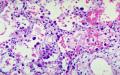

يصيب الالتهاب فصآ كامآ أو جزءآ منه أو أجزاء متفرقة من فصوص مختلفة، وتمتلتيء الحويصلات بالسوائل الالتهابية والصديد، ويمكن أن ينتقل الالتهاب إلى الدم مسببآ ما يسمى (Bacteremia) أو إلى السحايا مسببآ التهاب السحايا (Menengitis)

يحتاج بعض المرضى لإجراء فحوص مخبرية مثل صورة أشعة سينية للرئتين وفحص شامل للدم، بالاضافة إلى تحليل للبلغم